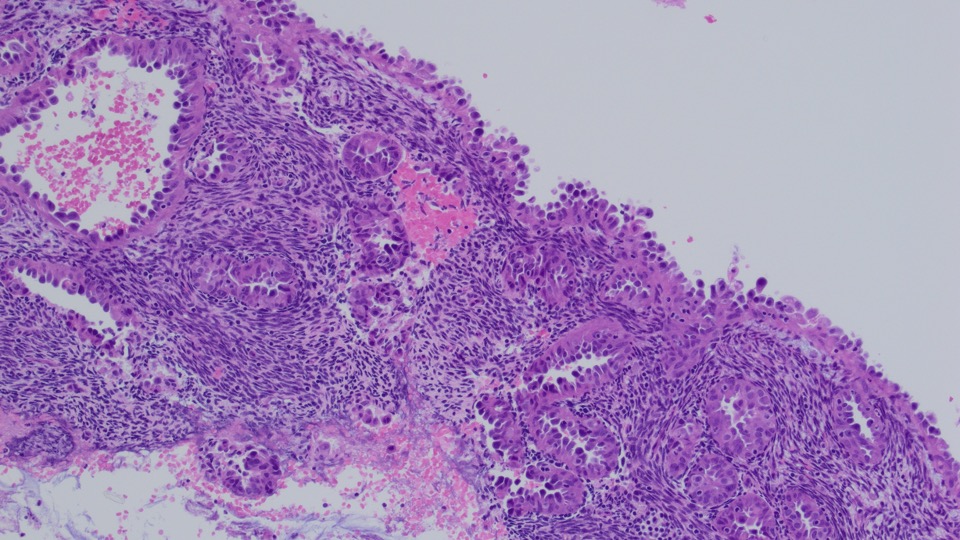

A 40 y/o euthyroid female and a 3 cm left-sided thyroid nodule incidentally found.